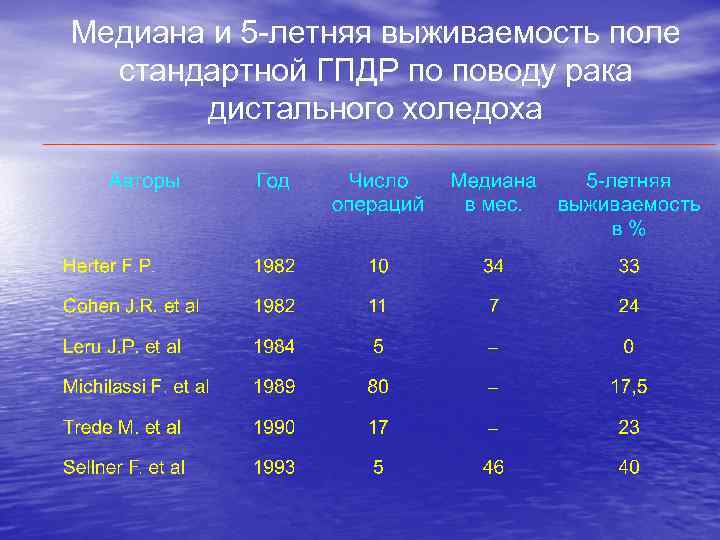

Медиана и 5 -летняя выживаемость поле стандартной ГПДР по поводу рака дистального холедоха